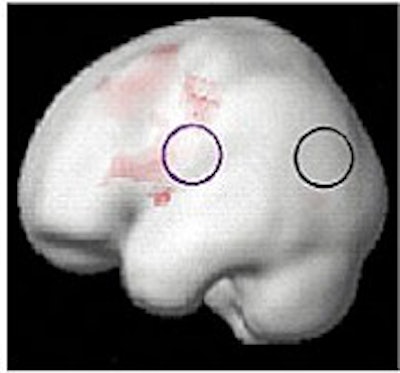

At the beginning of the study, MRI scans of the 20 dyslexic subjects contrasted sharply with those of the 12 normal readers in the control group; the dyslexic subjects' scans showed a lack of activity in the language-critical temporal regions of the brain.

Brain function in child with no reading disability (top); brain function in child with developmental dyslexia (middle); children with dyslexia show increased brain function after training (below). Images courtesy of Elise Temple, Ph.D.

At the end of the eighth week, the investigators found that, among the dyslectic subjects, areas of the brain critical to reading skills had become activated, and had begun to function more normally. Other regions of the brain also showed activity on the MRI scans, suggesting a gradual compensatory process that would help the dyslexic subjects learn to read more fluently.